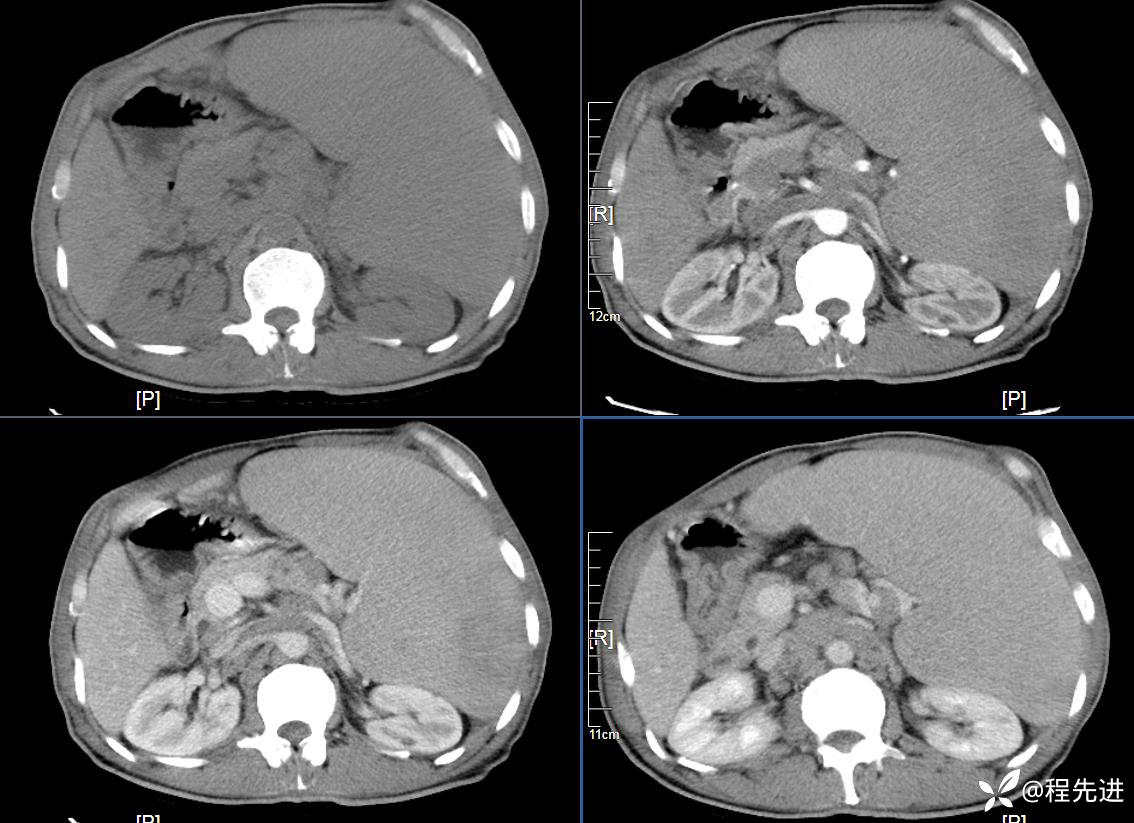

患者性别:男

患者年龄:59岁

简要病史:体检发现脾脏肿大半月

CT平扫及增强3期: